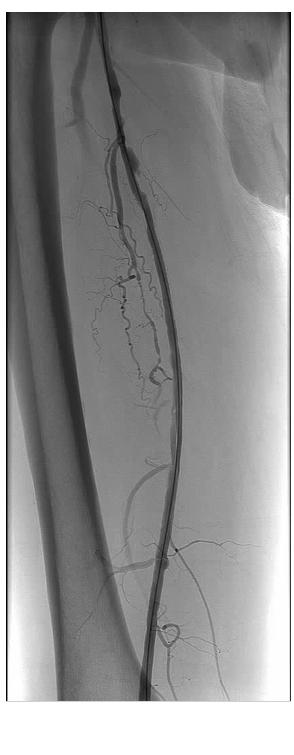

Noting both significant lesion length (~18 cm) and ostial location without calcification in our patient, we anticipated that a re-entry device might be successful (if necessary) and proceeded with antegrade probing of the CTO using an 0.035-inch angled Glidewire (Terumo, Somerset, NJ) and Seeker catheter (Bard, Tempe, AZ). As the wire could not be tracked in a straight line, we formed a loop and gently dissected subintimally to just above the knee, at which point we were able to maneuver into the reconstituted SFA.

A single 20-cm length self expanding stent was placed and post-dilated with a good result. Though a re-entry device was readily available, conventional methods proved successful in this case.